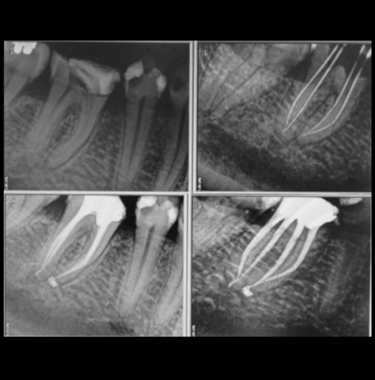

Parodontologie pour l'omnipraticien

Diagnostic et traitement